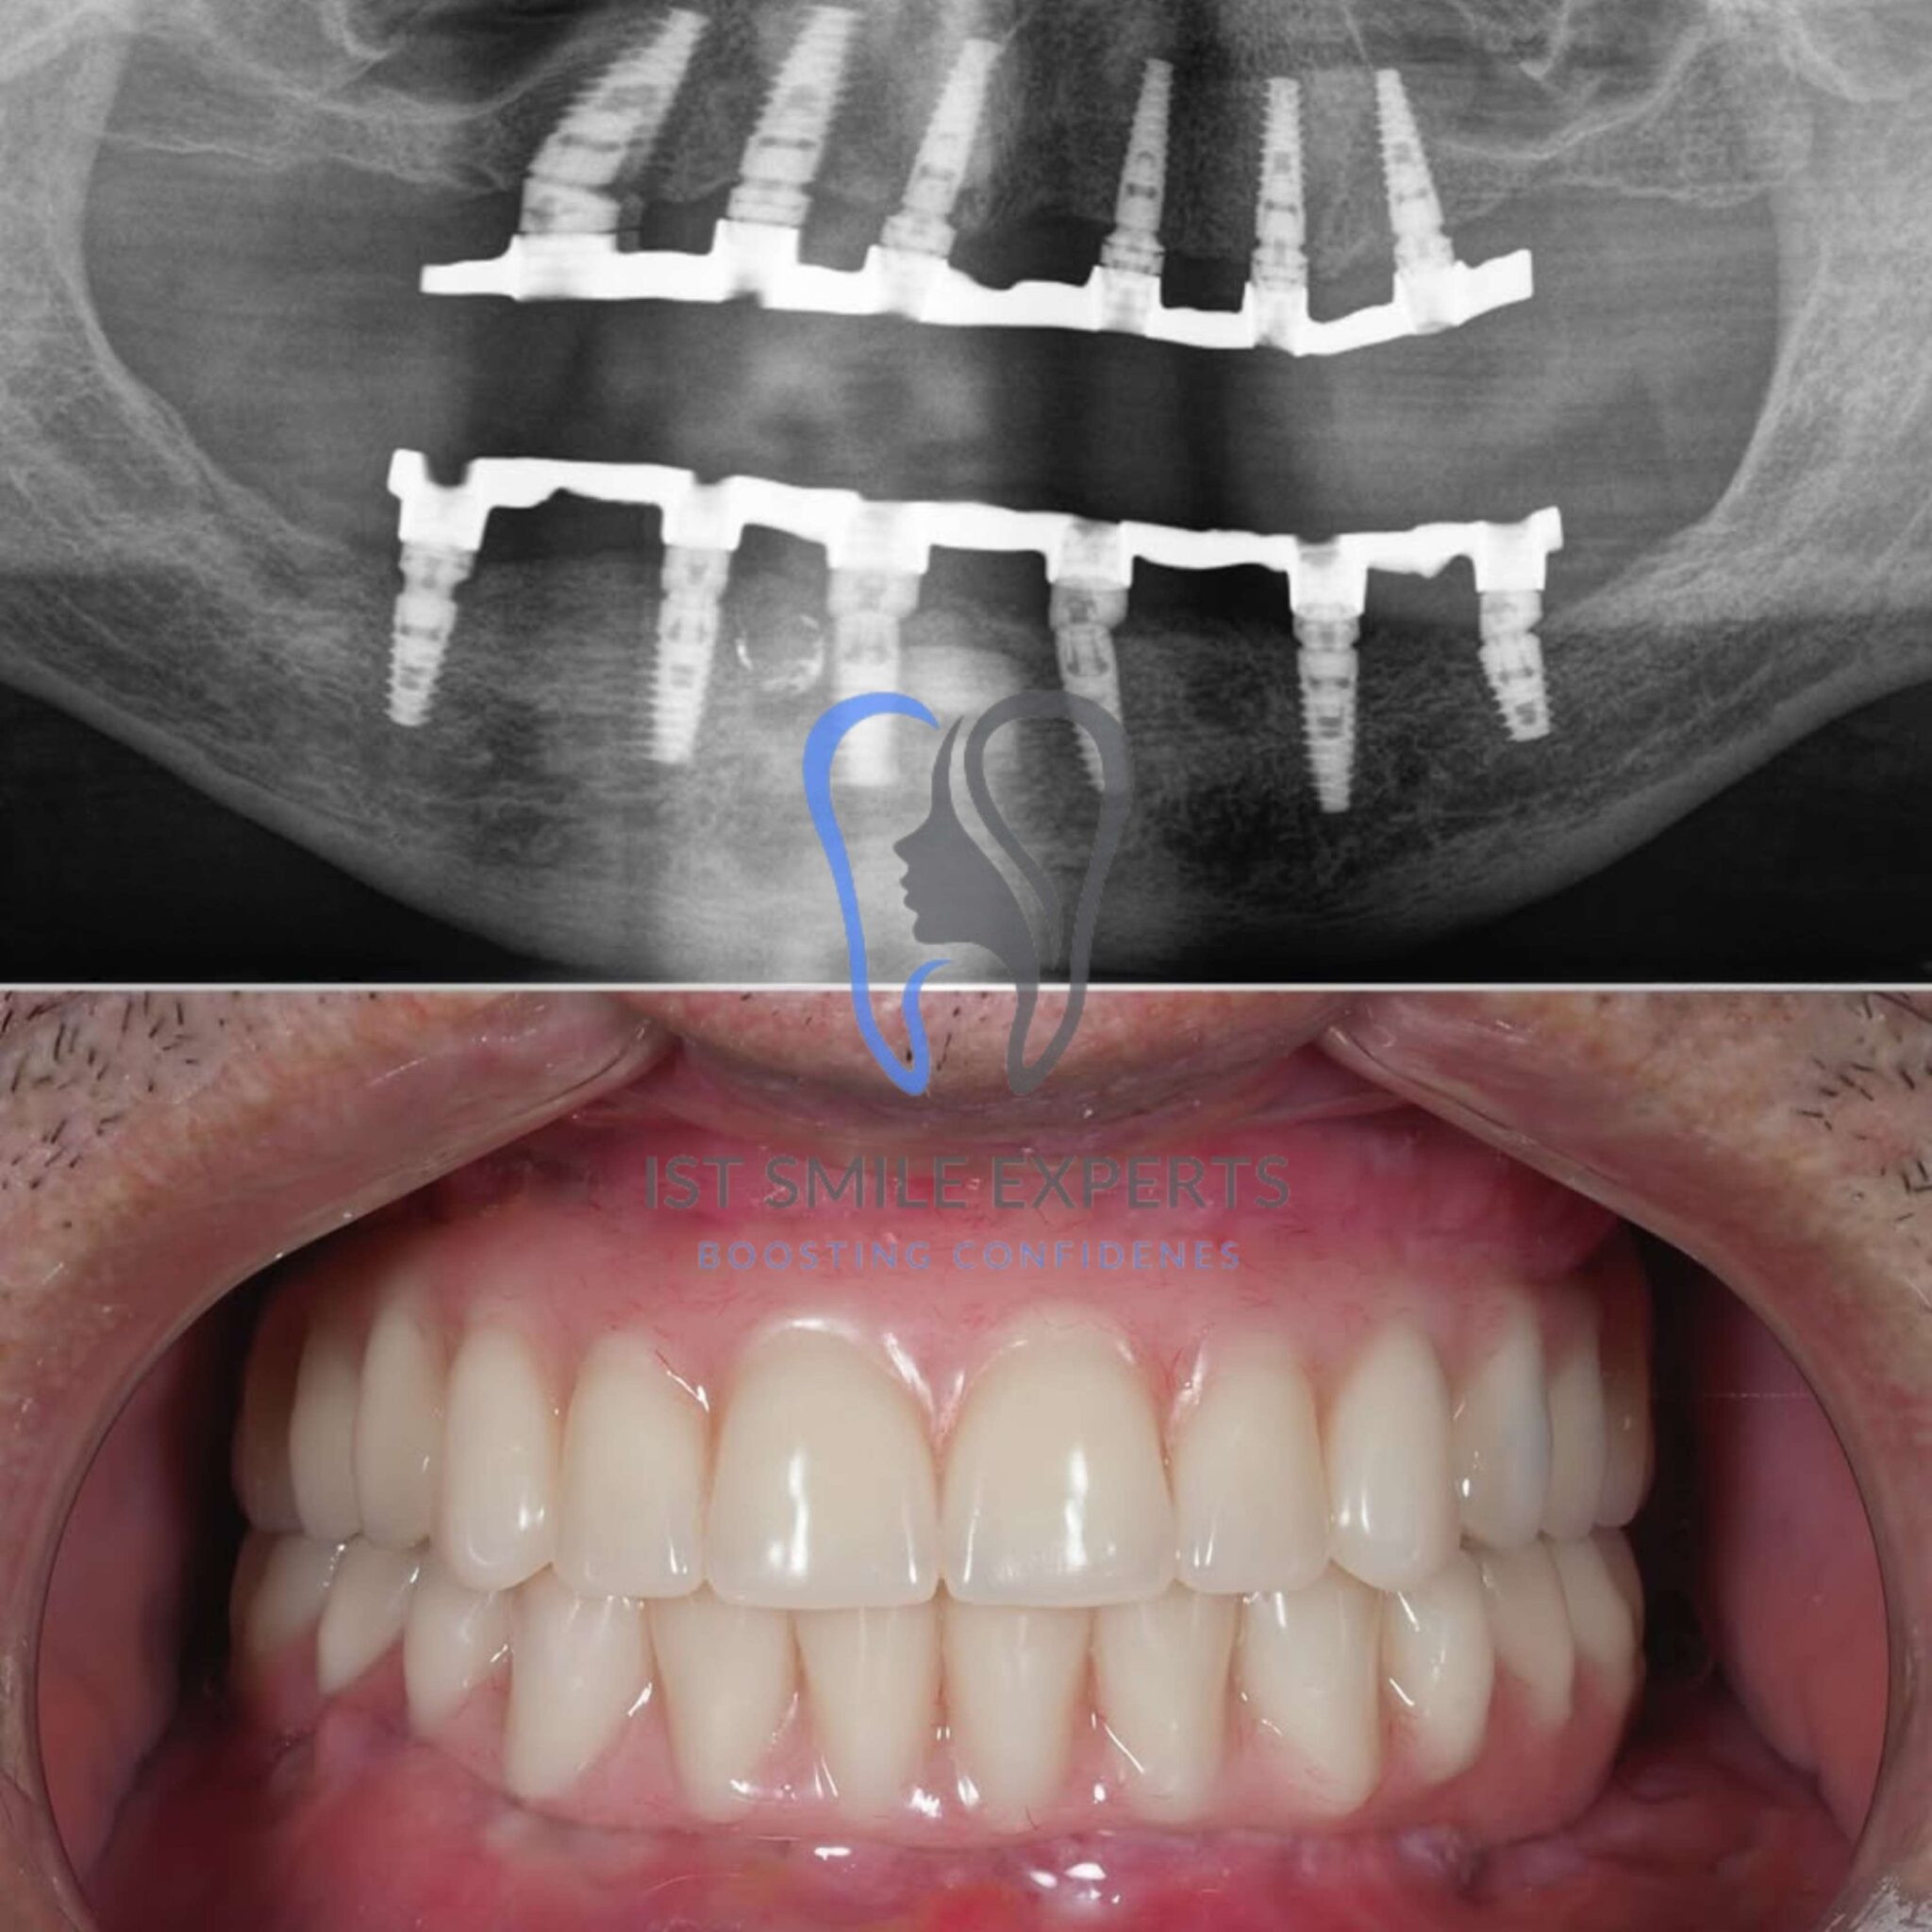

Full mouth dental implants, often referred to as All-on-4, All-on-6, or full arch implants, provide a superior alternative to traditional removable dentures. Our specialists design them to replace an entire arch of missing teeth with a fixed, natural-looking set of teeth. Consequently, this innovative solution offers unparalleled stability, comfort, and aesthetic appeal.

This surgical phase involves placing premium German or Swiss dental implants into your jawbone. Our surgeons perform this procedure under local anaesthesia. Moreover, we often attach a temporary set of teeth immediately after, allowing you to leave with a functional smile on the same day.

Once healing is complete, you will return for your second visit. We will then securely attach your custom-designed, permanent full arch bridge. Ultimately, this is when your transformed smile comes to life.